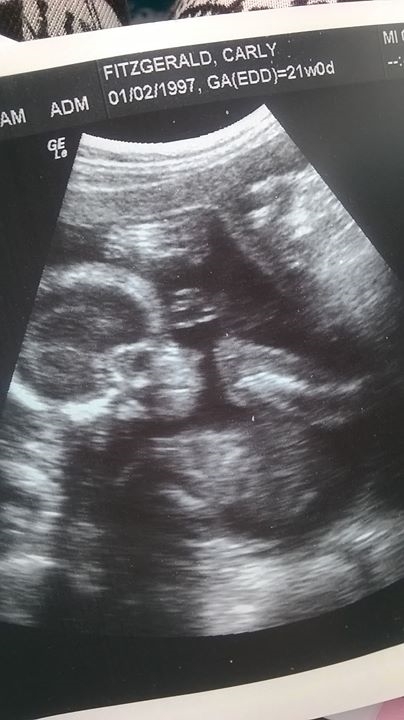

Hi everyone just wanted to know if you think my baby is a boy or girl , I am 21 weeks and was told it was a girl but there not always 100 % really hope its a girl!!

Carly all you r pics show babies face is that right? :) Can you post your 13 week pics for us?

I'm unable to zoom in your pics without losing the detail on my computer, but your 13 week pics have me leaning boy as there seems to alot going on down there. If you start a thread in the ultrasound guessing section hopefully somebody will be able to see alittle more clearly :) Post all pics and video you may have from the 13 week mark ok :)